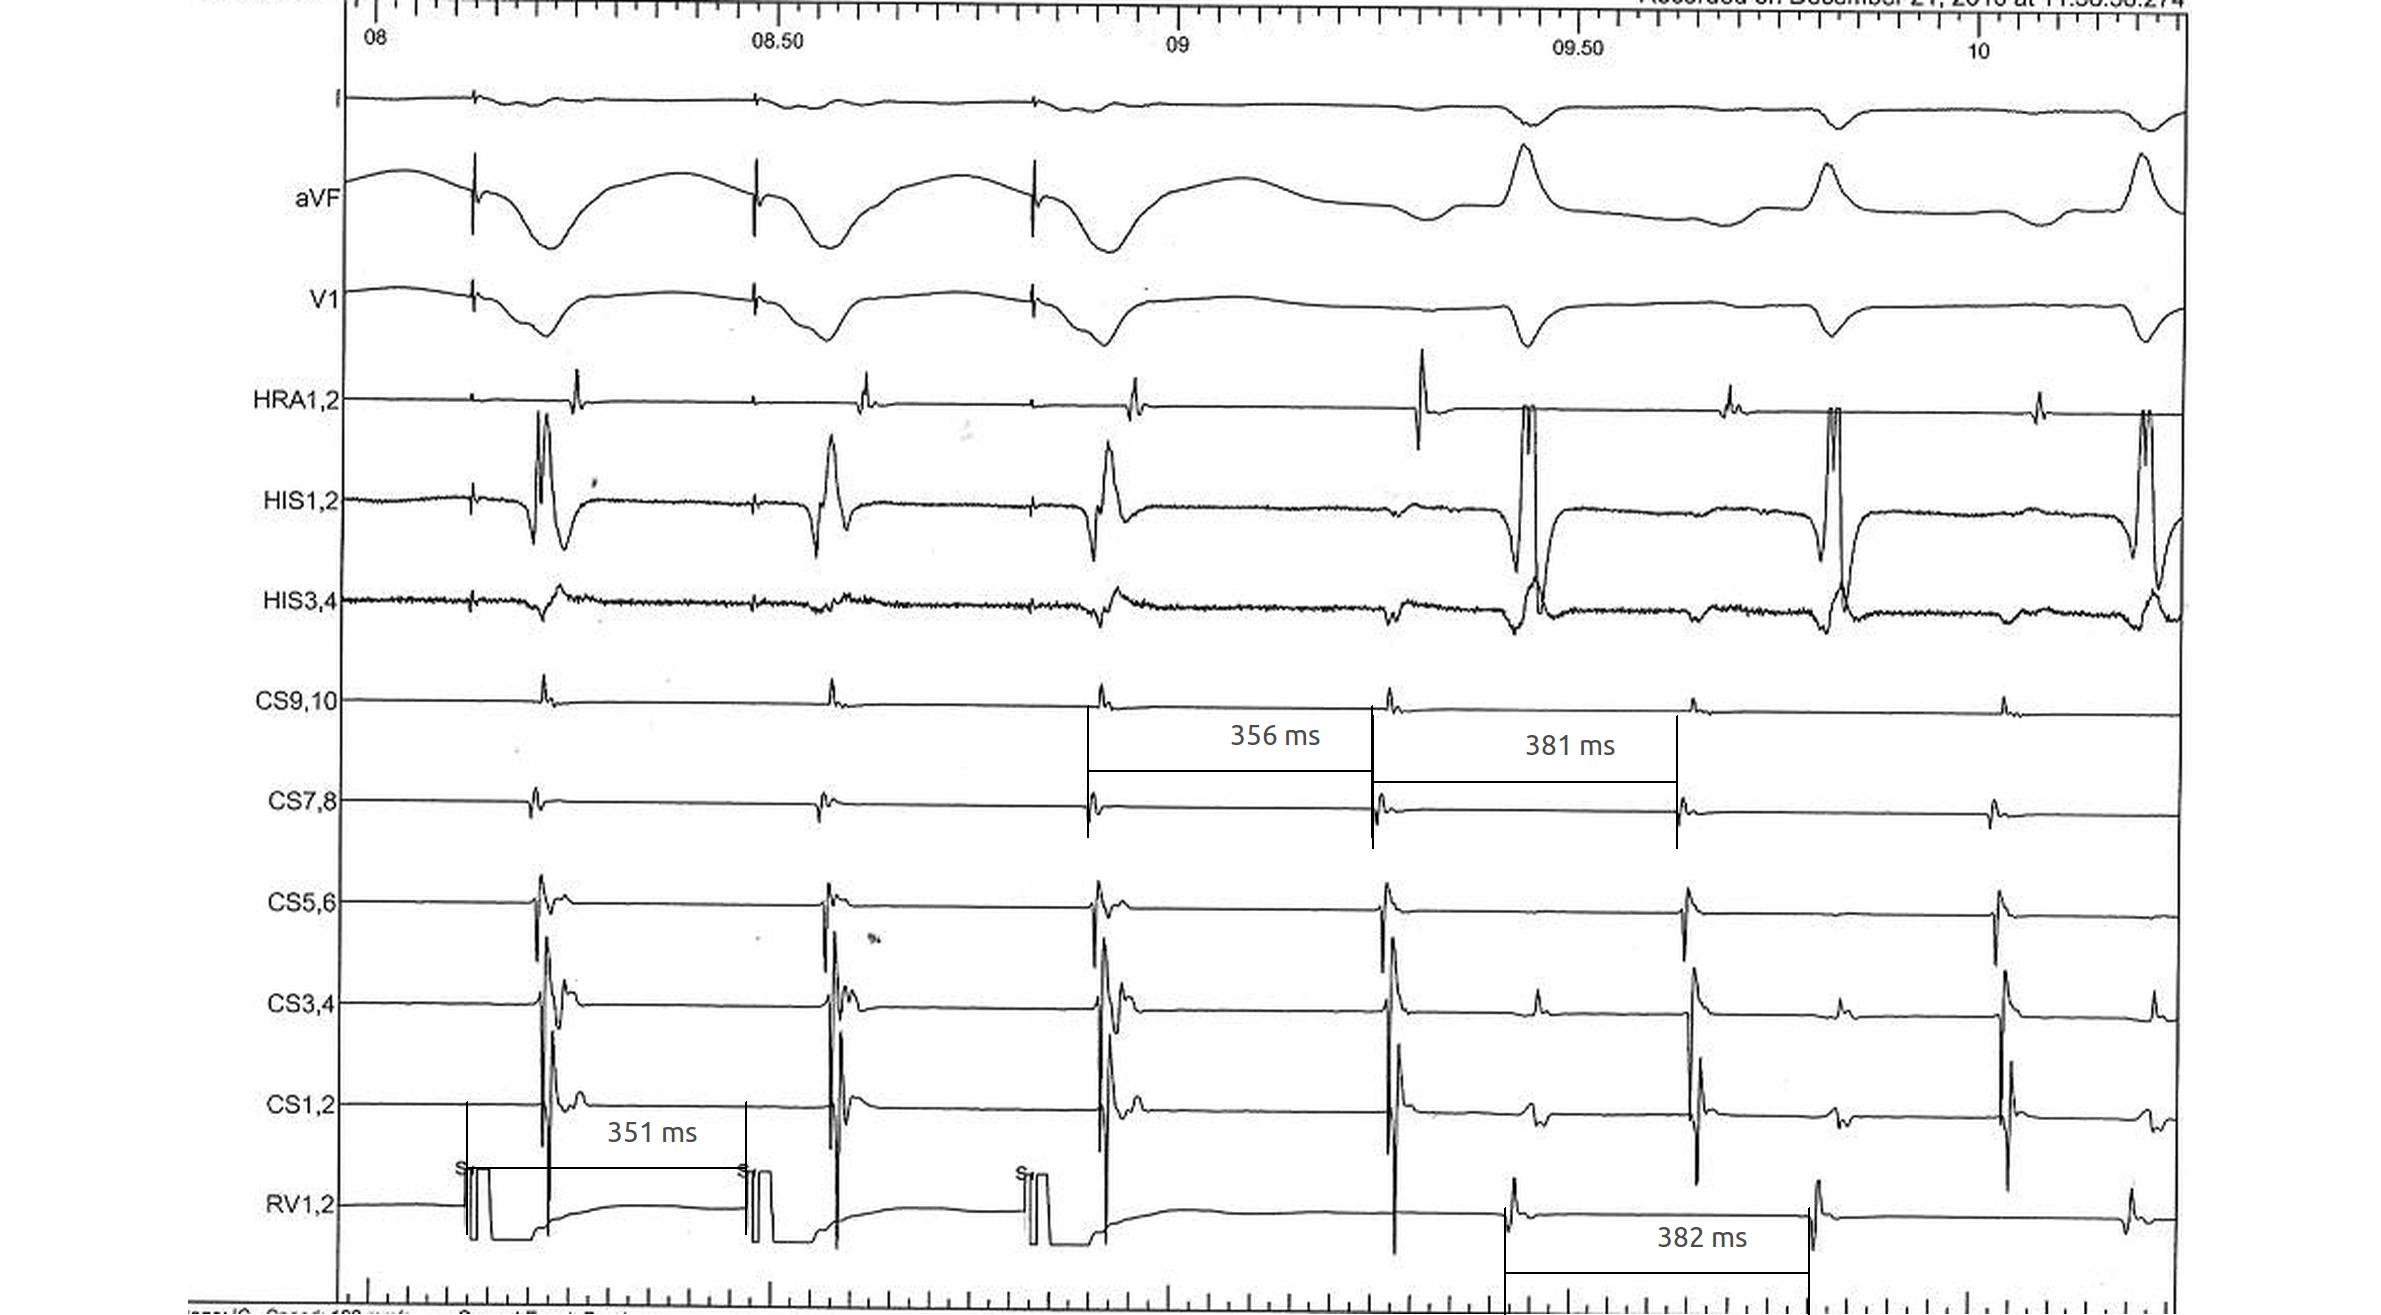

RV pacing in narrow QRS tachycardia - Rule out (or in) AT

vav.jpg

vav_measurements_atrium_entrain.jpg

RV pacing in narrow QRS tachycardia.

pseudoVAAV.png

Why all this fuss about measurement ?

pseudo_vaav_measurements.jpg

RV pacing in AT - VAAV

VAAV.jpg

RV pacing in narrow QRS tachycardia - AVNRT / AVRT

vav_measurements_ppi.jpg